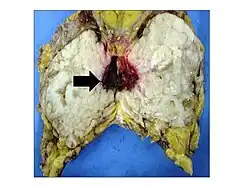

Anatomopathological results of phyllodes tumor.

Gross image of an excised phyllodes tumor.